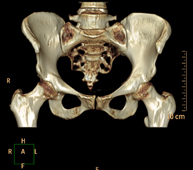

- TC Pelvis ósea Exploración radiológica que mediante un sistema de rayos X y detectores que giran alrededor del paciente, reconstruyendo las imágenes por ordenador (TC Multidetector), permite el estudio de huesos, músculos y articulaciones de la pelvis. Exploración radiológica que mediante un sistema de rayos X y detectores que giran alrededor del paciente, reconstruyendo las imágenes por ordenador (TC Multidetector), permite el estudio de huesos, músculos y articulaciones de la pelvis.

- TC Caderas Exploración radiológica que mediante un sistema de rayos X y detectores que giran alrededor del paciente, reconstruyendo las imágenes por ordenador (TC Multidetector), permite el estudio de huesos, músculos y articulaciones de la cadera. Exploración radiológica que mediante un sistema de rayos X y detectores que giran alrededor del paciente, reconstruyendo las imágenes por ordenador (TC Multidetector), permite el estudio de huesos, músculos y articulaciones de la cadera.

- TC Pelvis Prueba diagnóstica que consiste en obtener imágenes bi y tridimensionales de la pelvis de alta definición anatómica (estructuras óseas, estructuras vasculares, vejiga, útero y ovarios, próstata y vesículas seminales, uréteres, etc.) mediante el empleo de un equipo de TC (Tomografía Computarizada). La mayoría de estudios requieren el empleo de contraste yodado. Prueba diagnóstica que consiste en obtener imágenes bi y tridimensionales de la pelvis de alta definición anatómica (estructuras óseas, estructuras vasculares, vejiga, útero y ovarios, próstata y vesículas seminales, uréteres, etc.) mediante el empleo de un equipo de TC (Tomografía Computarizada). La mayoría de estudios requieren el empleo de contraste yodado.